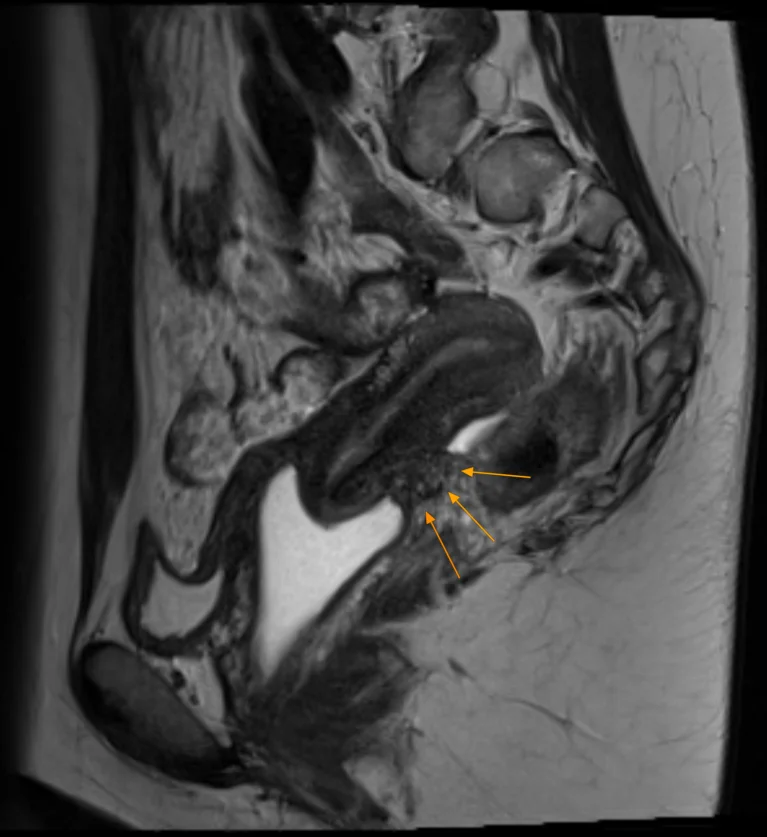

Nodule d’endométriose profonde du torus utérin avec spots hémorragiques | |||